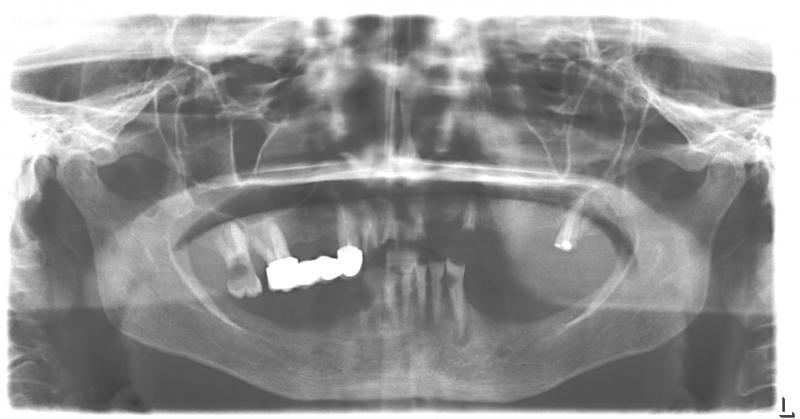

Фото →Установка 10 имплантантов на беззубую челюсть с помощью компьютерной программы: Через 2 недели после операции